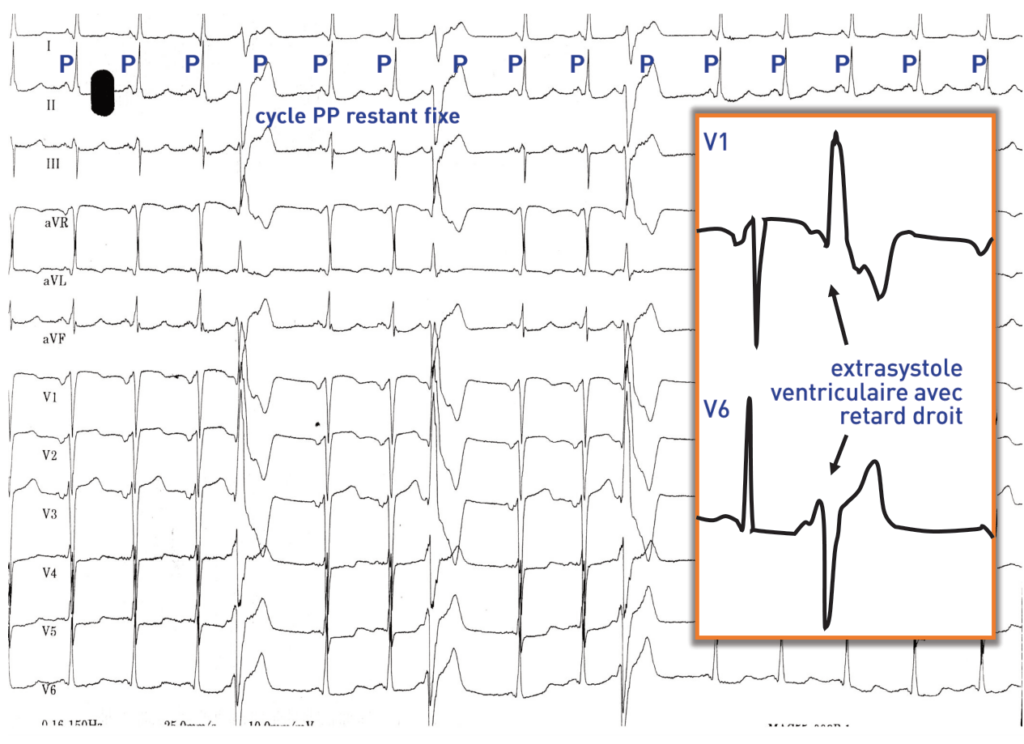

Sur l’électrocardiogramme, une extrasystole ventriculaire se caractérise par l’existence d’un QRS prématuré, ectopique, à QRS large (> 120 ms), sans association avec une activité atriale précédente. Les extrasystoles ventriculaires doivent plus être considérées comme un marqueur de risque qui doit orienter vers la recherche d’une cardiopathie et non comme un facteur de risque indépendant sur lequel il faut agir. La recherche d’une cardiopathie causale est donc un temps essentiel de la prise en charge.

Chez ce patient: 1) l’analyse du QRS conduit sur activité sinusale est très en faveur de l’existence d’une cardiopathie ischémique. On retrouve en effet, des signes d’hypertrophie auriculaire gauche mais également des signes de séquelle de nécrose antérieure confirmés par l’anamnèse et l’analyse des antécédents du patient. 2) la morphologie des extrasystoles est également en faveur de l’existence d’une cardiopathie. La largeur des complexes QRS ectopiques est importante et dépasse les 180 ms ce qui est évocateur d’une cardiopathie, les extrasystoles bénignes survenant sur coeur sain étant généralement plus fines (de l’ordre de 140 ms). Les extrasystoles ont un aspect crocheté, polyphasique et une amplitude relativement faible, autant d’arguments en défaveur d’un caractère bénin. La fragmentation des extrasystoles est considéré comme un facteur péjoratif car traduisant une propagation de l’influx électrique à travers un myocarde ventriculaire aux propriétés de conduction altérées, dans un myocarde cicatriciel ou fibrosé. Chez les patients avec myocardiopathie ischémique, le retard et l’axe des extrasystoles sont souvent dictés par la localisation de la séquelle de nécrose puisque ces extrasystoles sont soit le reflet d’une activité normale de cellules au fonctionnement altéré par l’ischémie, soit le résultat d’une réentrée autour de circuits à propagation lente de l’influx électrique dans les zones cicatricielles.